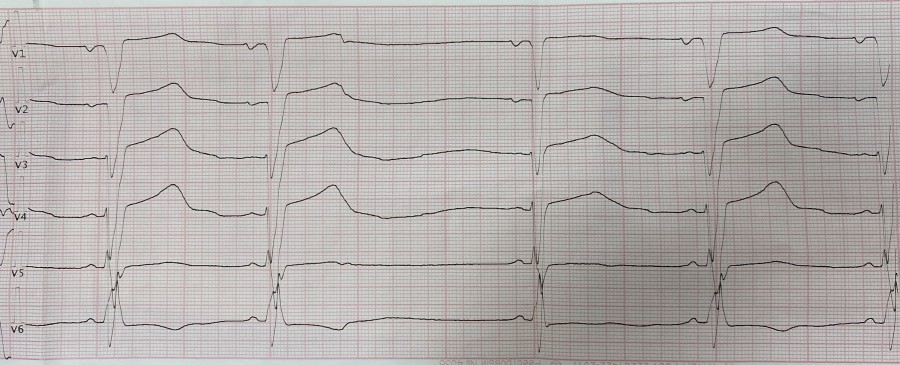

Блокированная ЭС на фоне рубцов

Вложения:

IMG_8846.jpg

IMG_8846.jpg [ 111.27 KiB | Просмотров: 20161 ]

IMG_8847.jpg

IMG_8847.jpg [ 108.77 KiB | Просмотров: 20161 ]